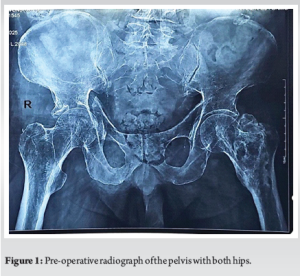

As a first investigation of choice, X-ray of the pelvis with both hips was taken, which revealed a right acetabular fracture with superomedial dome impaction (Gull sign) [4-6], quadrilateral plate involvement and central dislocation with break in the iliopectineal line (Fig. 1). Computed tomography (CT) of the pelvis with both hip joints was taken to get a better anatomy of the fracture pattern and to know the amount of comminution and for pre-operative planning (Fig. 2).